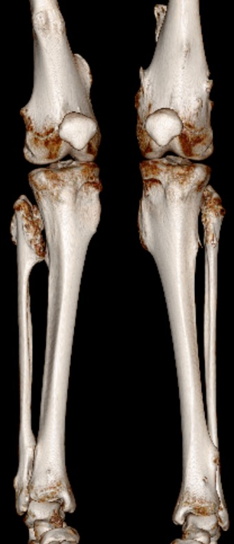

A 12-year-old girl reported pain in the lower limbs, wrists and knees 3 years ago. She evolved with leg pain when walking, edema and asymmetry of the legs and in the circumference of the knees. One year ago, a punctiform bone protuberance appeared near the right external malleolus. A maternal aunt was diagnosed with multiple osteochondromatosis. Physical examination: overall decrease in skeletal muscle strength, antalgic posture, swollen knees, painful limitation of knee movements, abdormal gait and fixed posture in valgus knees. Referred to Rheumatology due to suspicion of Juvenile Idiopathic Arthritis because she had deformities in the knees and pain in different joints; however, it was observed that there was no associated arthritis. Laboratory tests without alterations and computed tomography (CT) revealed the presence of multiple osteochondromas (Figure 1-3), indicating a bone metaplasia, compatible with the diagnosis of multiple osteochondromatosis.1,2

Figure 1 Three-dimensional CT showing multiple osteocondromas.